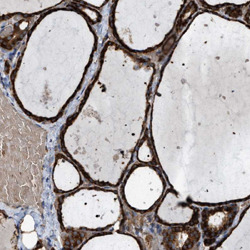

- Experimental details

- Immunohistochemical staining of human thyroid gland with SELM polyclonal antibody(Cat # PAB27474) shows strong cytoplasmic positivity in glandular cellsat 1:500-1:1000 dilution.

- Validation comment

- Immunohistochemistry (Formalin/PFA-fixed paraffin-embedded sections)